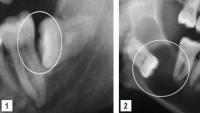

Decay Example

- Extensive decay affecting upper and lower impacted wisdom tooth

- Impaction of lower wisdom tooth leading to development of decay in the lower second molar

- Extensive decay affecting impacted lower wisdom tooth

Impacted Wisdom Teeth

Impacted wisdom teeth can also adversely affect the attachment of adjacent teeth or be associated with cystic lesions.

- Horizontally impacted wisdom tooth adversely affecting attachment of second molar

- Extensive cystic development around impacted lower wisdom tooth